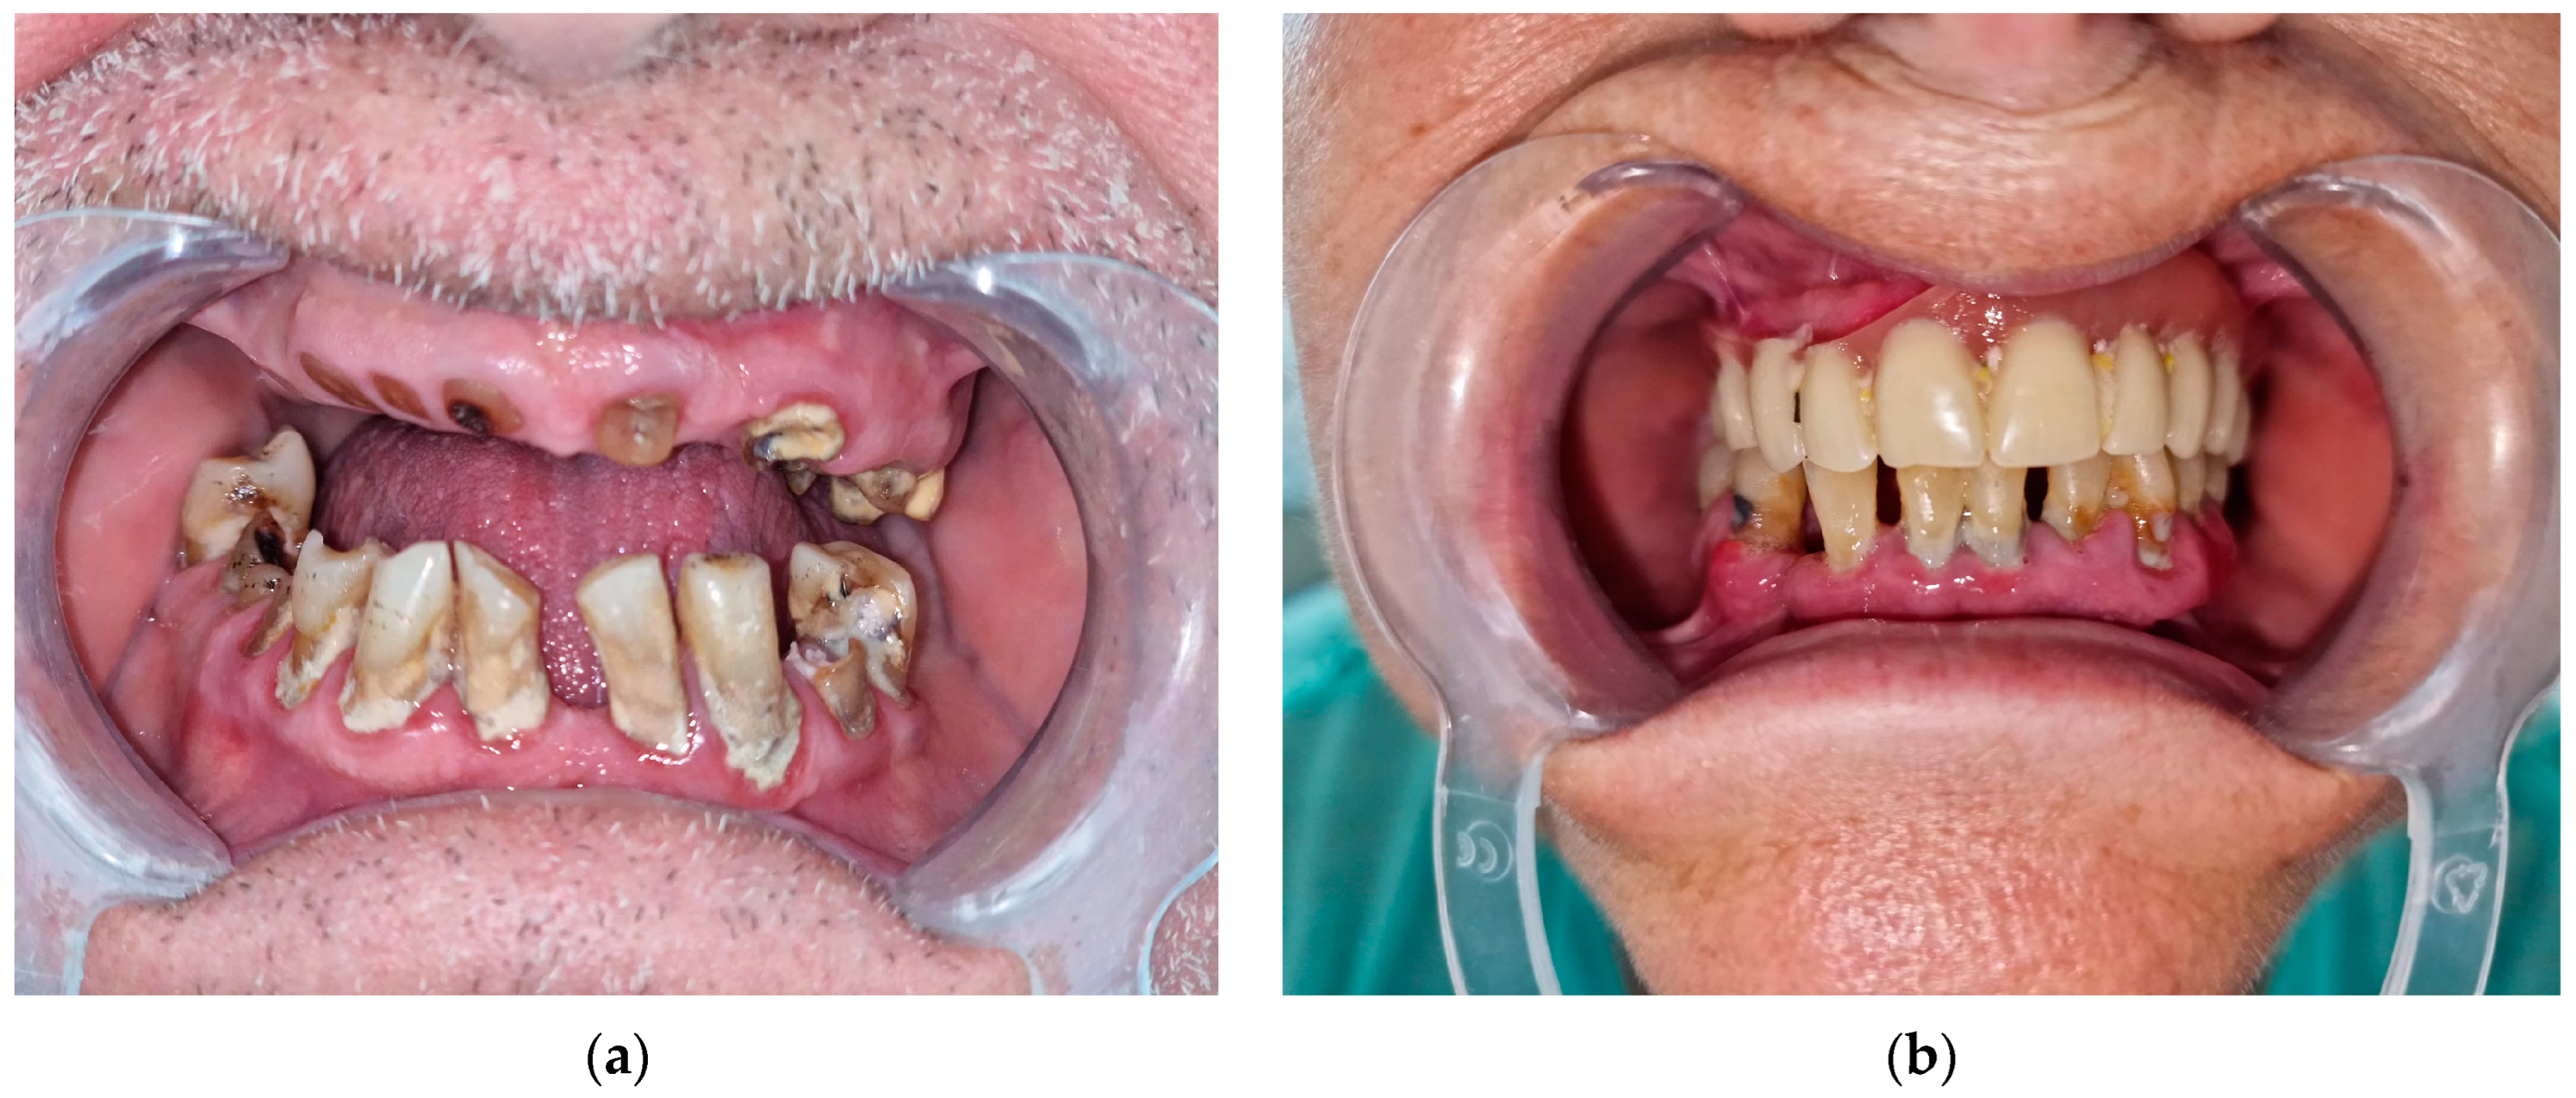

2.4. Evaluation of Dental Lesions